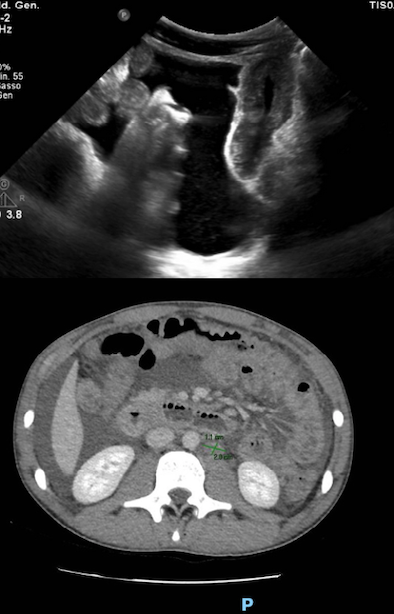

Lecografia addominale evidenziava la presenza di versamento ascitico e un diffuso ispessimento delle pareti intestinali sia tenuali che coliche (max 5 mm), con perdita di stratificazione. La TC addome confermava versamento ascitico esteso con spessore assiale massimo di 10 cm nello scavo pelvico e ispessimento parietale diffuso dal tratto distale dellesofago fino al tratto prossimale del retto, compatibile con panenterocolite; non mostrava segni di ostruzione intestinale, pneumoperitoneo, masse/pacchetti linfonodali e alterazioni delle strutture vascolari (Figura). Il liquido ascitico prelevato mediante paracentesi eco-guidata mostrava un alto contenuto proteico (> 3 g/dl), una spiccata cellularità di tipo eosinofilo (85%) e risultava sterile dal punto di vista microbiologico. La biopsia osteomidollare evidenziava un midollo ipercellulato con significativa espansione della serie eosinofila (23% della popolazione cellulare) senza caratteristiche morfologiche neoplastiche.